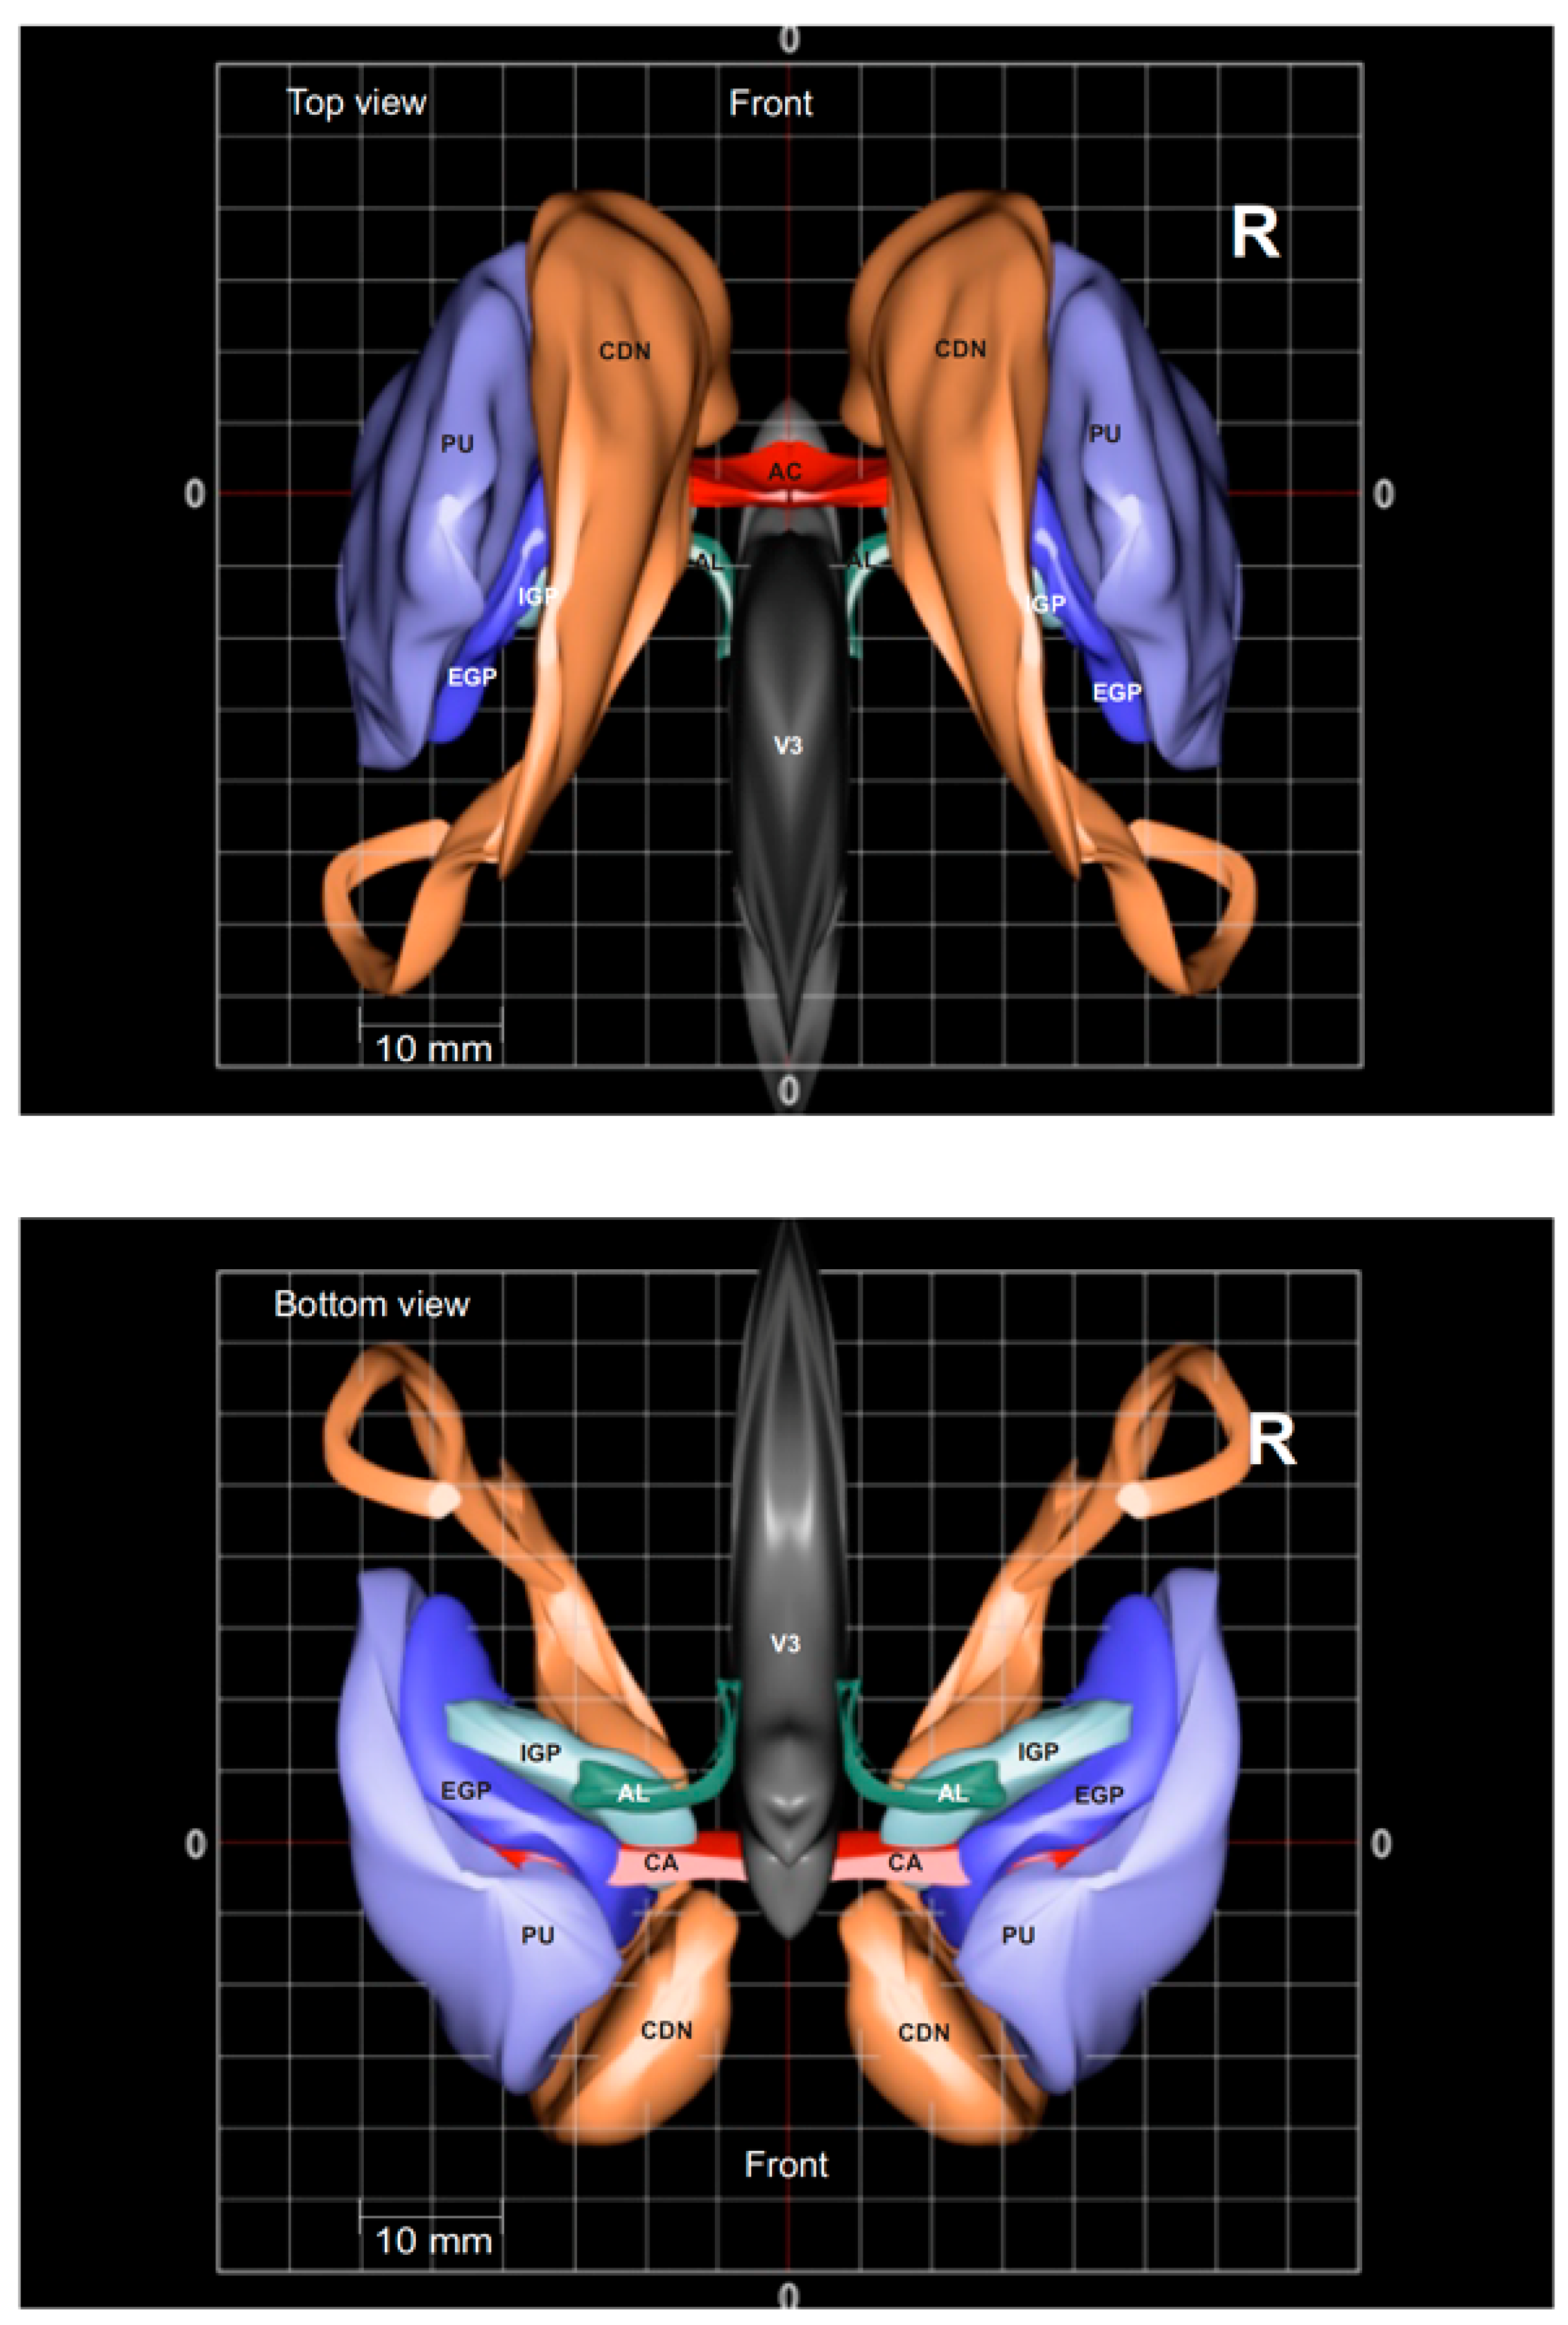

10. Three-Dimensional Rendered Atlases from Histological Sections and Multiatlas Collections

- Yelnik, J.; Bardinet, E.; Dormont, D.; Malandain, G.; Ourselin, S.; Tandé, D.; Karachi, C.; Ayache, N.; Cornu, P.; Agid, Y. A Three-Dimensional, Histological and Deformable Atlas of the Human Basal Ganglia. I. Atlas Construction Based on Immunohistochemical and MRI Data. Neuroimage 2007, 34, 618–638. [Google Scholar] [CrossRef]